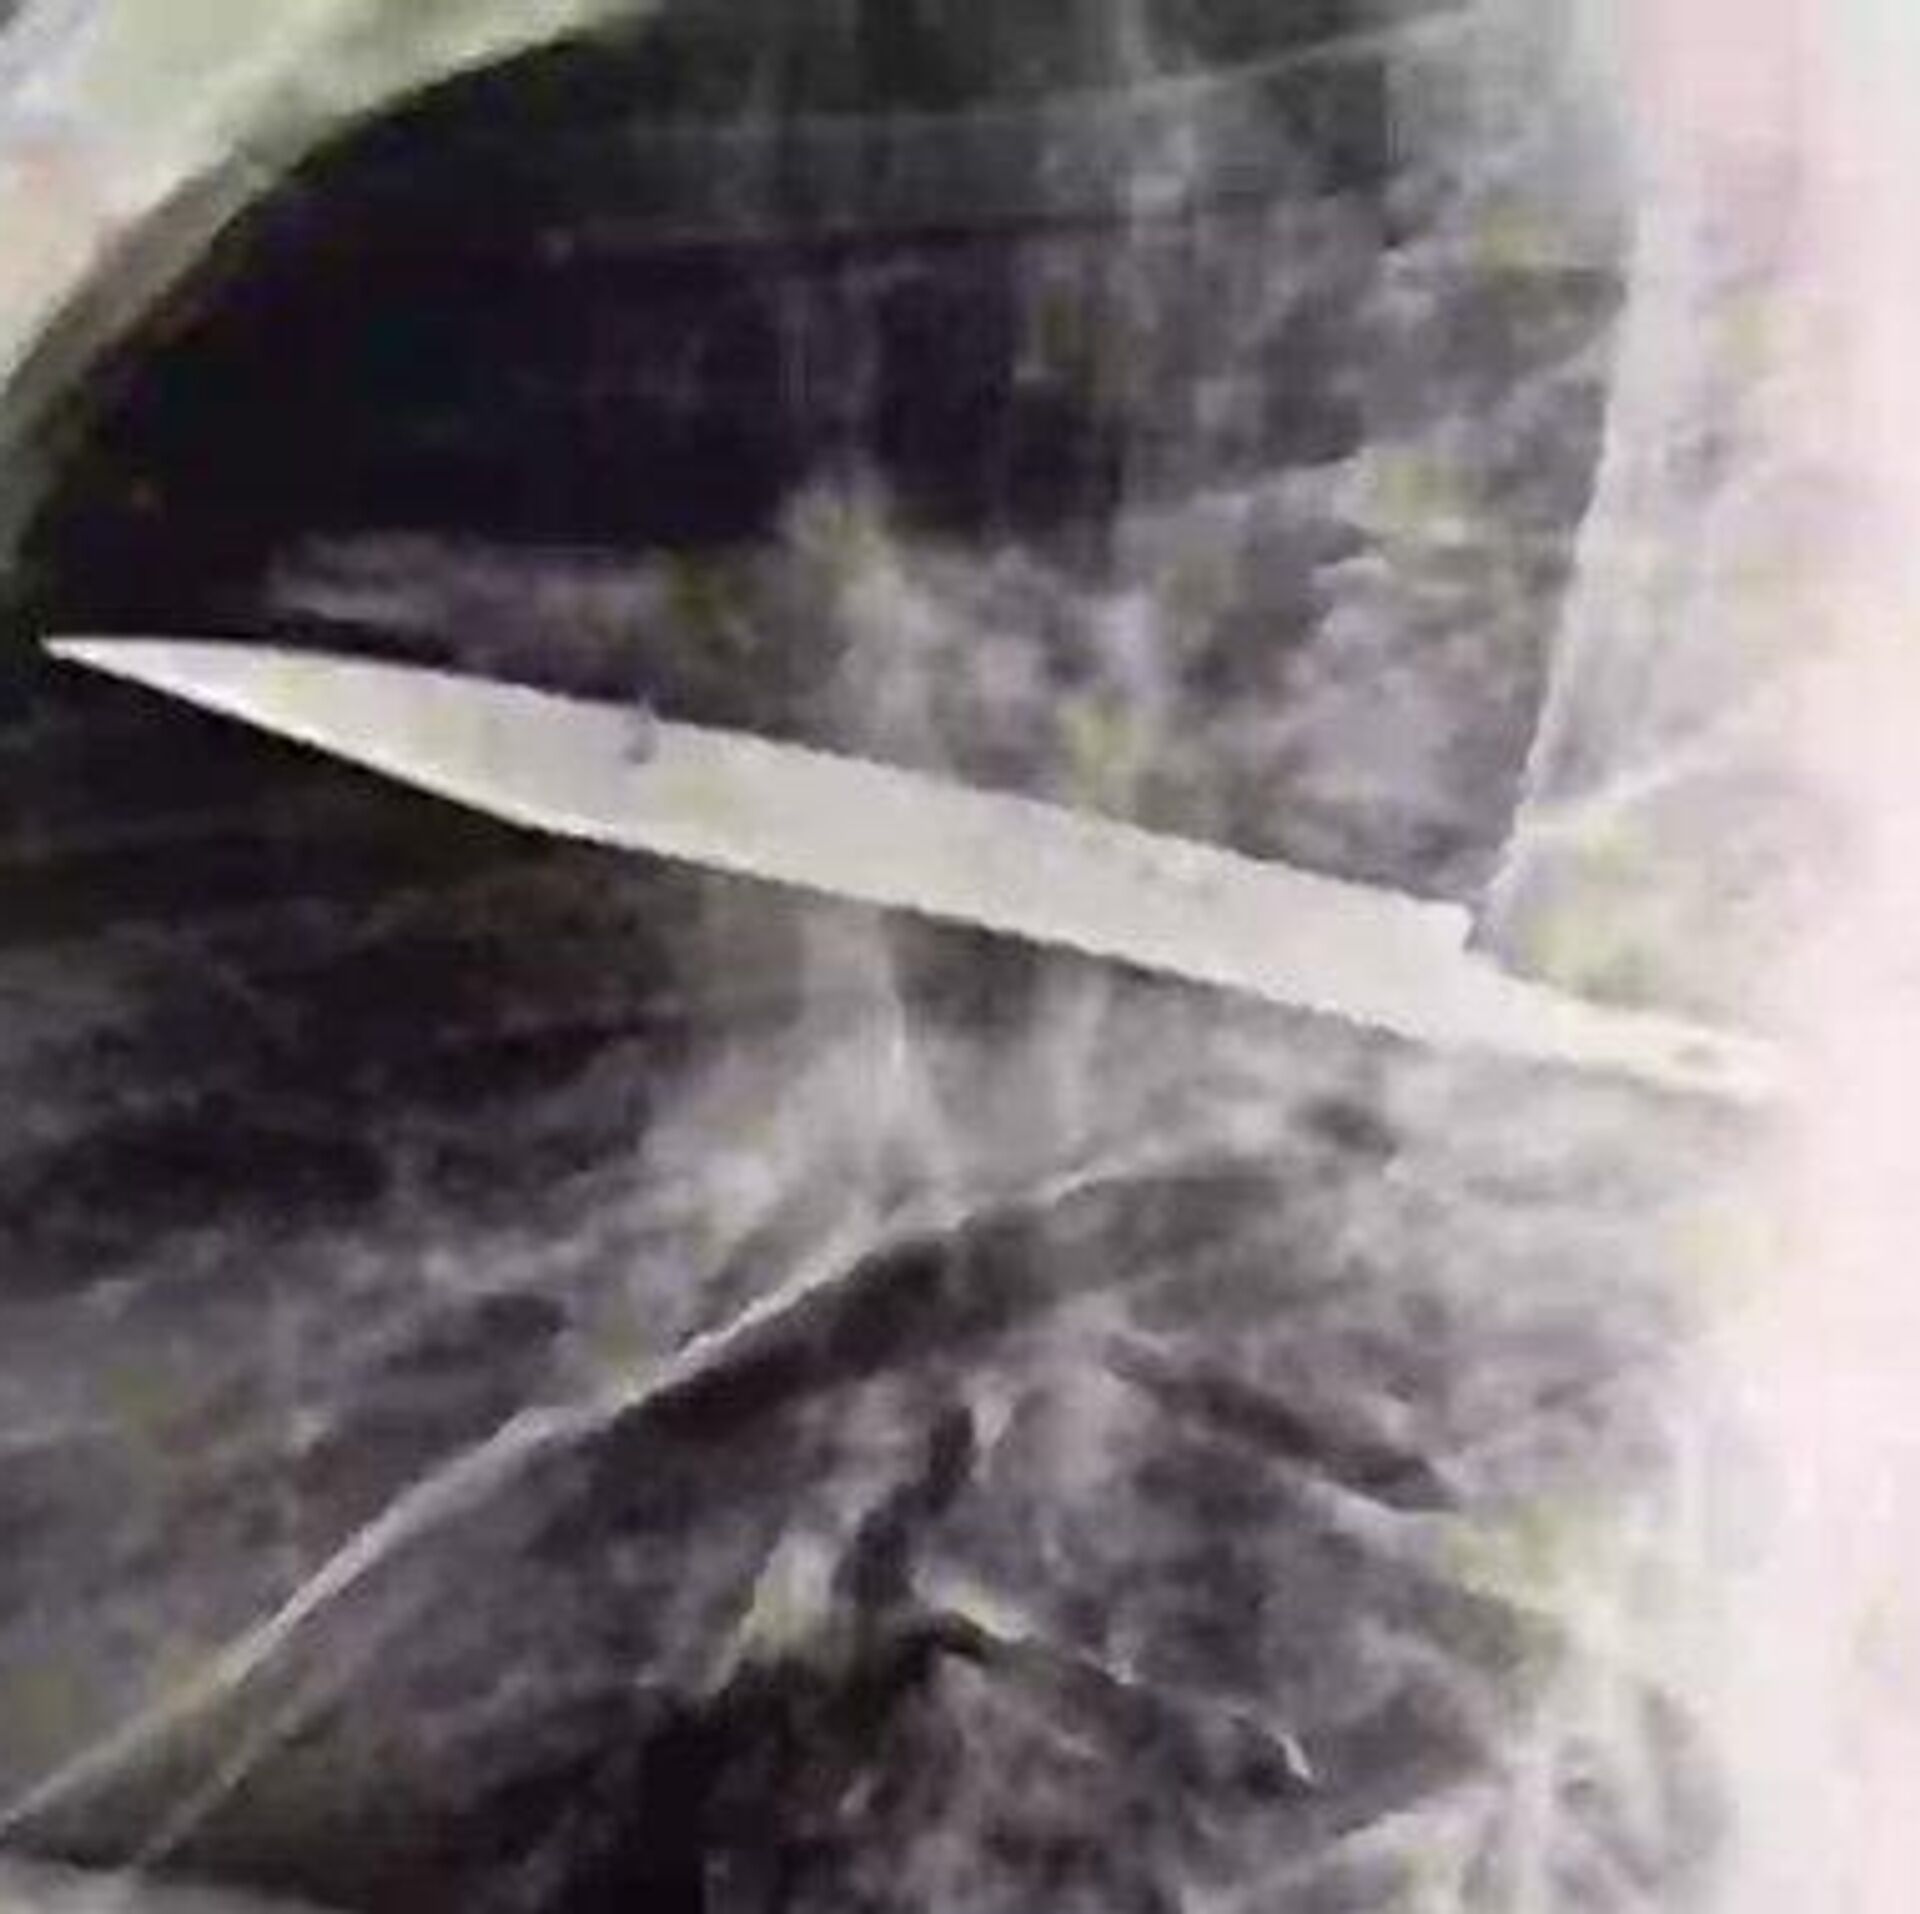

13:58 20.08.2025 (güncellendi: 14:53 20.08.2025) Tanzanya’da 44 yaşındaki bir adam, göğsünden irin gelmesi üzerine hastaneye gitti. Yapılan röntgen, inanılması güç bir gerçeği ortaya çıkardı. Göğsünde sekiz yıldır saplı bir bıçak olduğu anlaşıldı.

Tanzayalı 44 yaşındaki Adam, sağ göğsünden irin akmaya başlayınca enfeksiyon kaptığını düşündü. Ancak doktorlar muayene sırasında durumun çok daha farklı olduğunu fark etti. İlk başta sağlıklı görünen adamın röntgeninde göğsünde büyük bir bıçak tespit edildi.

Hasta, doktorlara sekiz yıl önce bir kavgaya karıştığını ve vücudunun birçok yerinden kesikler aldığını anlattı. O dönem uzak bir bölgede yaşadığı için yalnızca yüzeysel tedavi gördü ve hiç röntgen çektirmedi. Olayın ardından yıllarca göğsünden irin akana kadar hiçbir belirti göstermedi.

Doktorlar hemen ameliyat kararı aldı. Bıçak başarıyla çıkarıldı ve adam sadece 10 gün içinde taburcu edildi. Uzmanlar bunun büyük bir şans olduğunu belirterek, 'Bu kadar uzun süre bıçakla yaşamak ölümcül sonuçlar doğurabilirdi' dedi.

Tıp uzmanlarına göre adamın hayatta kalmasının sebebi, vücudunun bıçağı koruyucu bir kapsül içine alarak iltihaplanmayı geciktirmesiydi. Ancak zamanla bu sistem zayıfladı ve irin akmasıyla birlikte ciddi komplikasyonlar başladı.